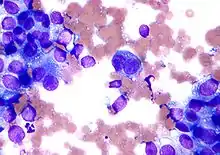

Micrograph of a Field stain showing malignant melanoma.